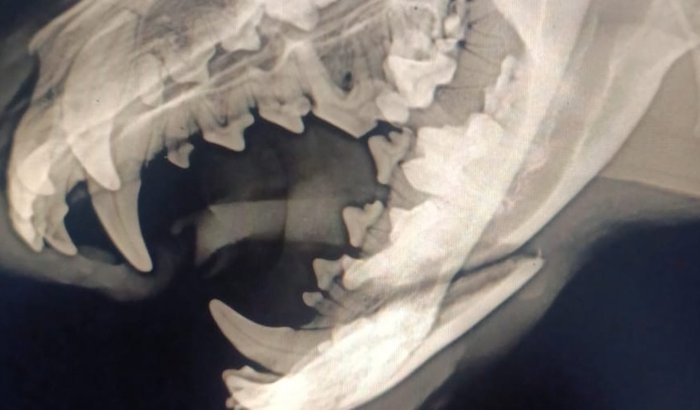

Boa noite pessoal, queria agradecer desde já a todas as pessoas que se disponibilizaram em ajudar com as despesas do " Negão "Meu cachorro foi atropelado na noite de ontem ,estamos fazendo o possível para a sua recuperação mas não tenho todo o dinheiro para arcar com as despesas do veterinário 🥺 por isso vim pedir a ajuda de quem puder, qualquer valor é bem-vindo, o "Negão " é um cachorro que foi resgatado em situação de risco,cuido dele há 05 anos e temos por ele um sentimento de família, conto com a ajuda de todos que se sensibilizar com a nossa situação 😭🙏🏻🙏🏻